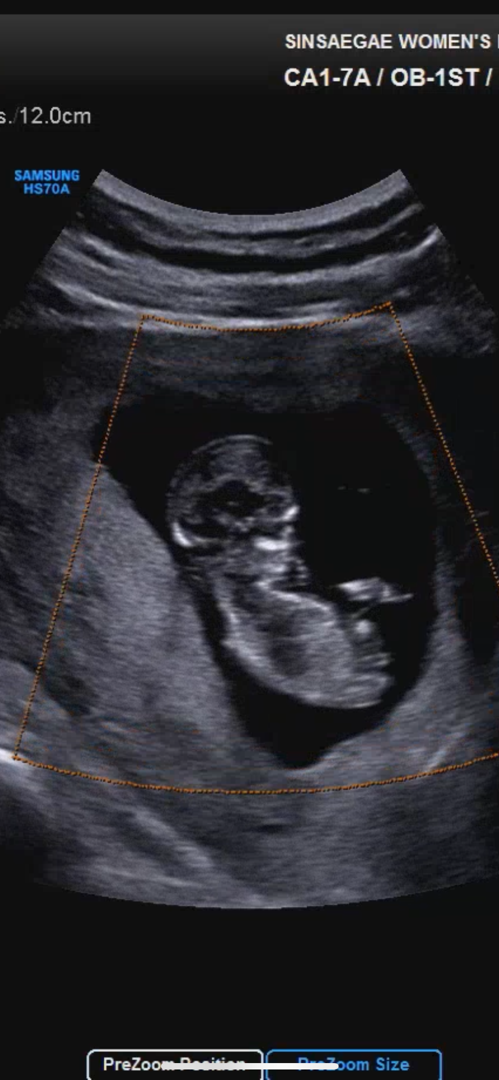

기형아 1차 검사!

다행히 목투명다 1.2~1.3으로 정상 범위라네요! 걱정 많이했는데 다행입니다 ㅎㅎ혹시 이 자세에도 각도법 볼수있나요?